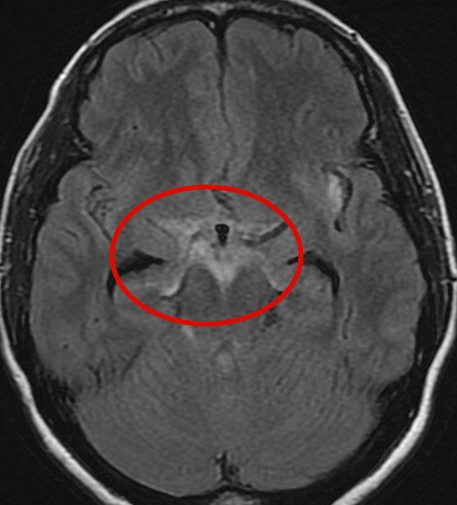

くも膜下出血の症例

高血圧症のある40代の男性です。仕事中に突然後頭部を殴られたかのような激痛を覚え、職場からそのまま横浜脳神経内科を受診しました。MRI検査を行ったところ、

脳底槽という脳の隙間に、血液成分(白く写っている部分)を認めました。くも膜下出血を発症していることが分かり、救急車を依頼して専門病院へ搬送させていただきました。